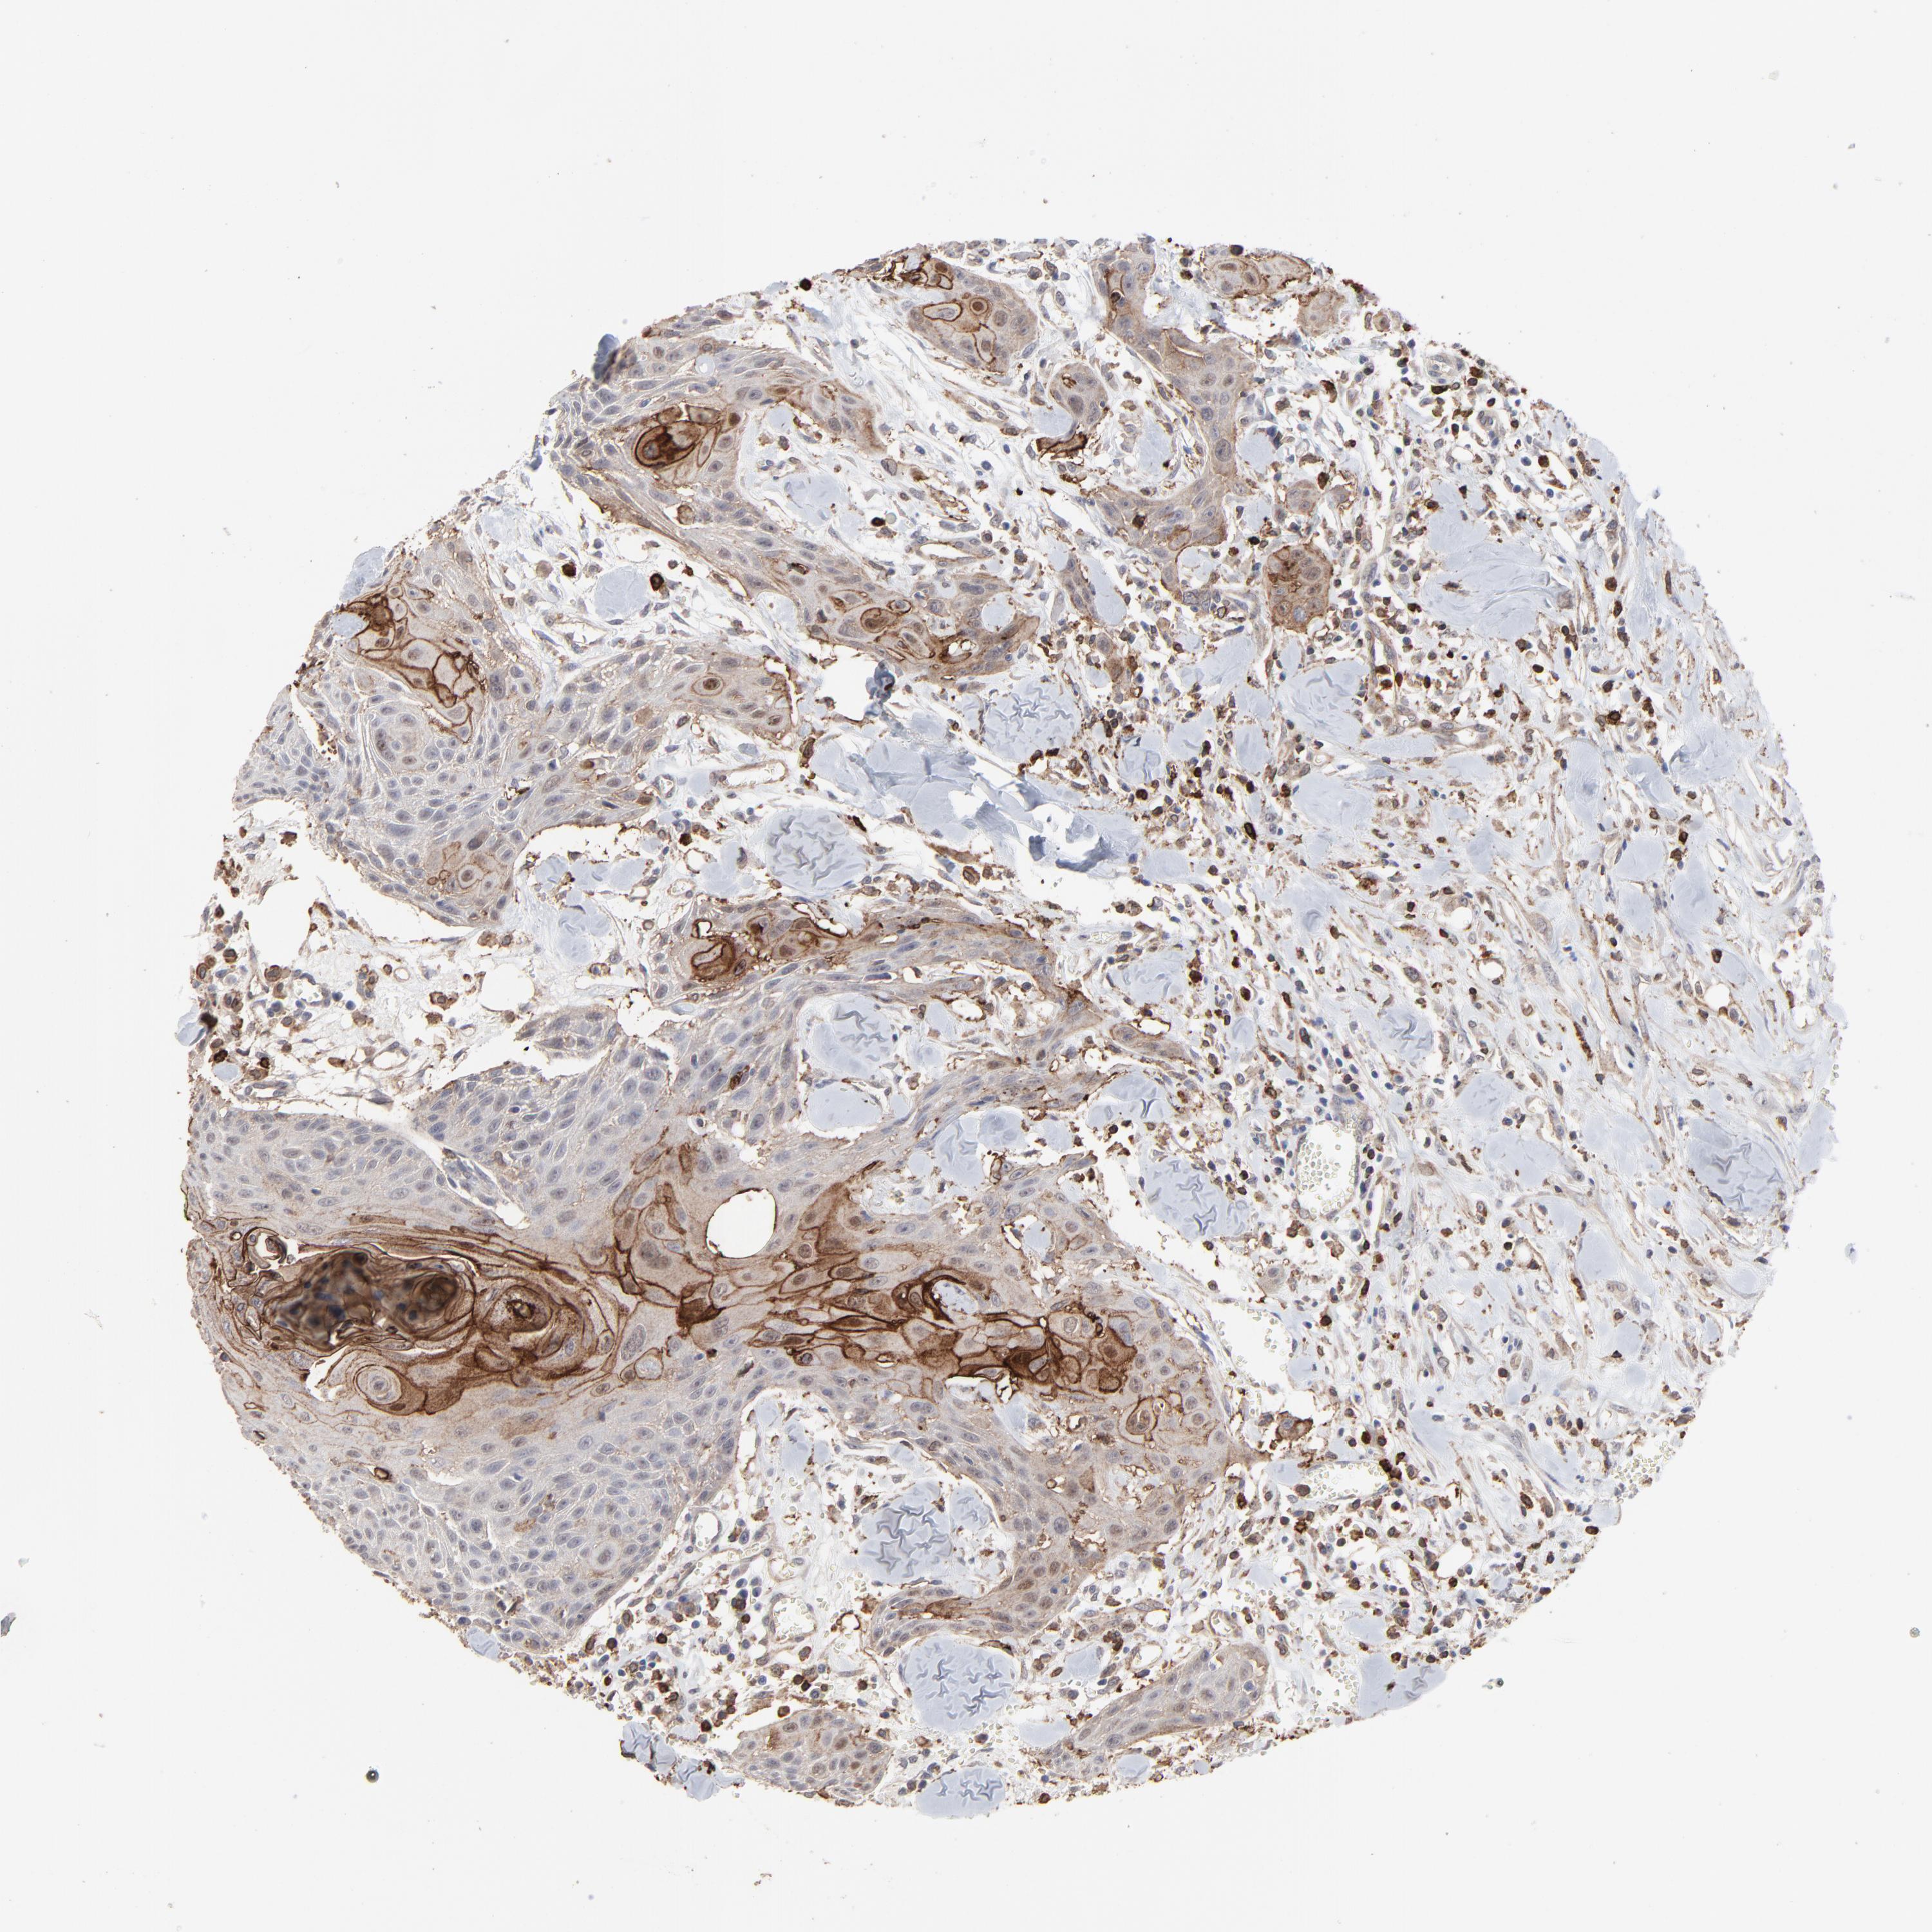

HEAD AND NECK CANCER - Protein expressioni

A mouse-over function shows sample information and annotation data. Click on an image to view it in a full screen mode. Samples can be filtered based on level of antibody staining by selecting one or several of the following categories: high, medium, low and not detected. The assay and annotation is described here.

Antibody stainingi

Antibody staining in the annotated cell types in the current human tissue is reported as not detected, low, medium, or high, based on conventional immunohistochemistry profiling in selected tissues. This score is based on the combination of the staining intensity and fraction of stained cells.

Each image is clickable and will lead to virtual microscopy that enables deeper exploration of all samples and also displays staining intensity scores, fraction scores and subcellular localization as well as patient and tissue information for each sample.

Antibody HPA003193

Staining

High

Medium

Low

Not detected

Intensity

Strong

Moderate

Weak

Negative

Quantity

>75%

75%-25%

<25%

None

Location

Nuclear

Cytoplasmic/membranous

Cytoplasmic/membranous,nuclear

Squamous cell carcinoma, NOS

Squamous cell carcinoma, metastatic, NOS